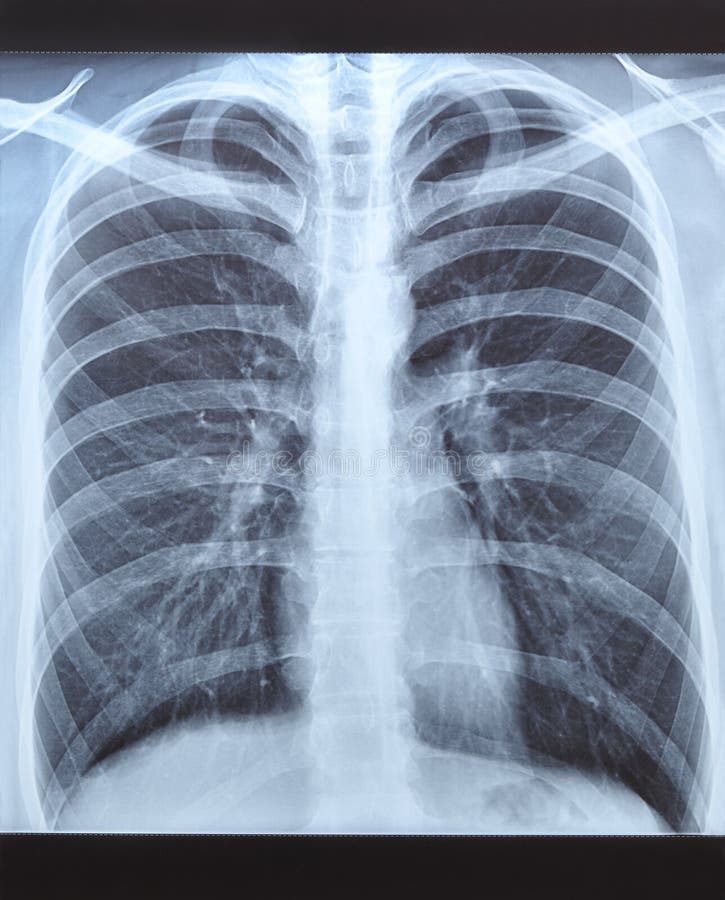

Нормальная рентгенограмма легких: что нужно знать

Раздел: Мудрость в объективе